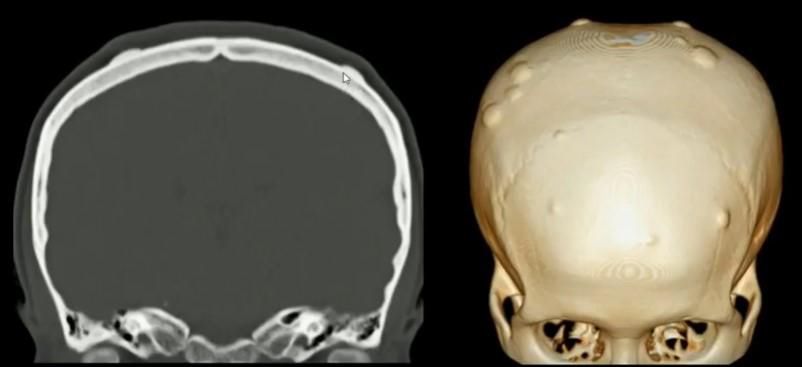

Іноді, при пухлинах, які явно неможливо видалити або при сумнівах в природі внутрішньомозкової пухлини, проводиться діагностична операція біопсія пухлини головного мозку. Це втручання полягає в тому, що через невеликий фрезевий отвір в кістках черепа спеціальний інструментарій підводиться до пухлинного вузла і береться зразок тканини пухлини для гістологічного і, або, гістохімічного дослідження.